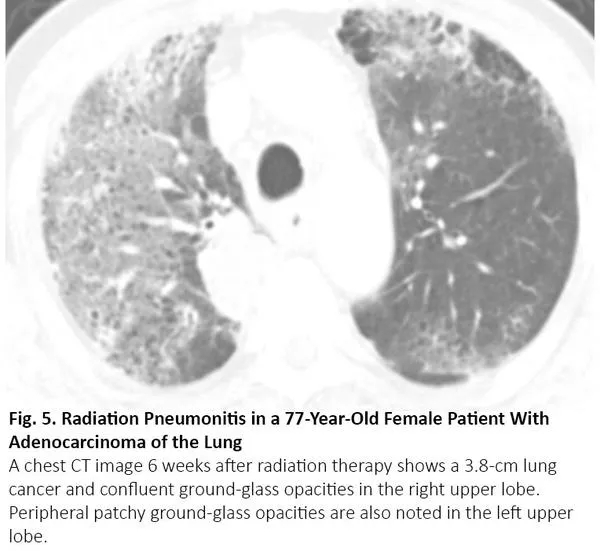

吸烟增加罹患肺癌和特发性肺纤维化(IPF)的风险,特发性肺纤维化患者罹患肺癌的风险会增加。当患者接受手术或放疗时,若特发性肺纤维化急性加重,CT可呈现双肺弥漫性或外周磨玻璃影,17与COVID-19肺炎相同(图7)。

图7. 一位72岁的小细胞肺癌女性患者出现特发性肺纤维化急性加重